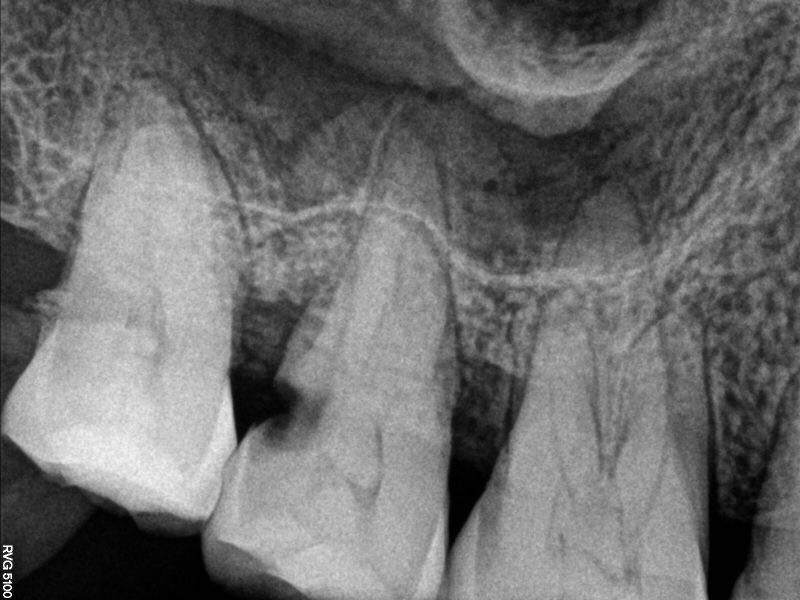

17牙冷++,叩+-,远中探及龋坏,x线片远中大面积龋坏近髓腔,根尖未见明显暗影,髓腔内大面积钙化影像

行17牙局麻下开髓失活,两周复诊,去封后见髓腔内大块髓石,p5超声去除大块髓石,根管口完全堵塞,继续去除髓石致近中壁侧穿